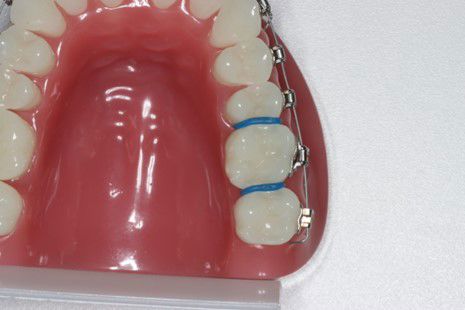

Placeres mellem 6-års tænderne hvis der skal sættes et bånd rundt om 6-års tænderne.

Sidder på tandbånd og ligger langs ganen, for at holde eller ændre på 6-års tænderne i overkæben. Desuden kan den holde eller øge tandbuens bredde.

Det vil være nødvendigt at isætte separationselastikker ved 6-års tænderne.